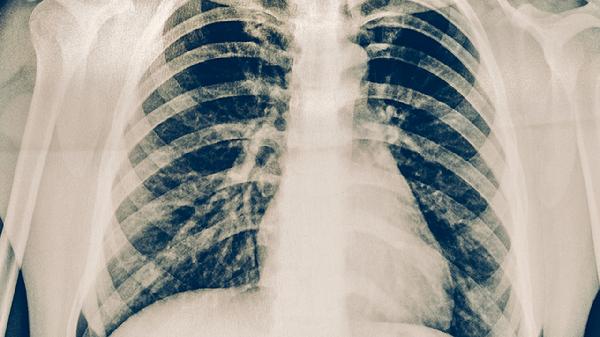

揭秘肺结核的5大典型症状

肺结核的典型症状主要有咳嗽、咳痰、咯血、胸痛、发热。肺结核是由结核分枝杆菌感染引起的慢性传染病,建议出现相关症状时及时就医。

肺结核患者应注意加强营养,多摄入高蛋白、高维生素食物如鸡蛋、牛奶、新鲜蔬菜水果等。保持居室通风良好,避免去人群密集场所。严格遵医嘱用药,完成全程治疗,不可擅自停药。适当进行散步等轻度运动,但避免剧烈活动。定期复查胸部影像学和痰结核菌检查,监测治疗效果。